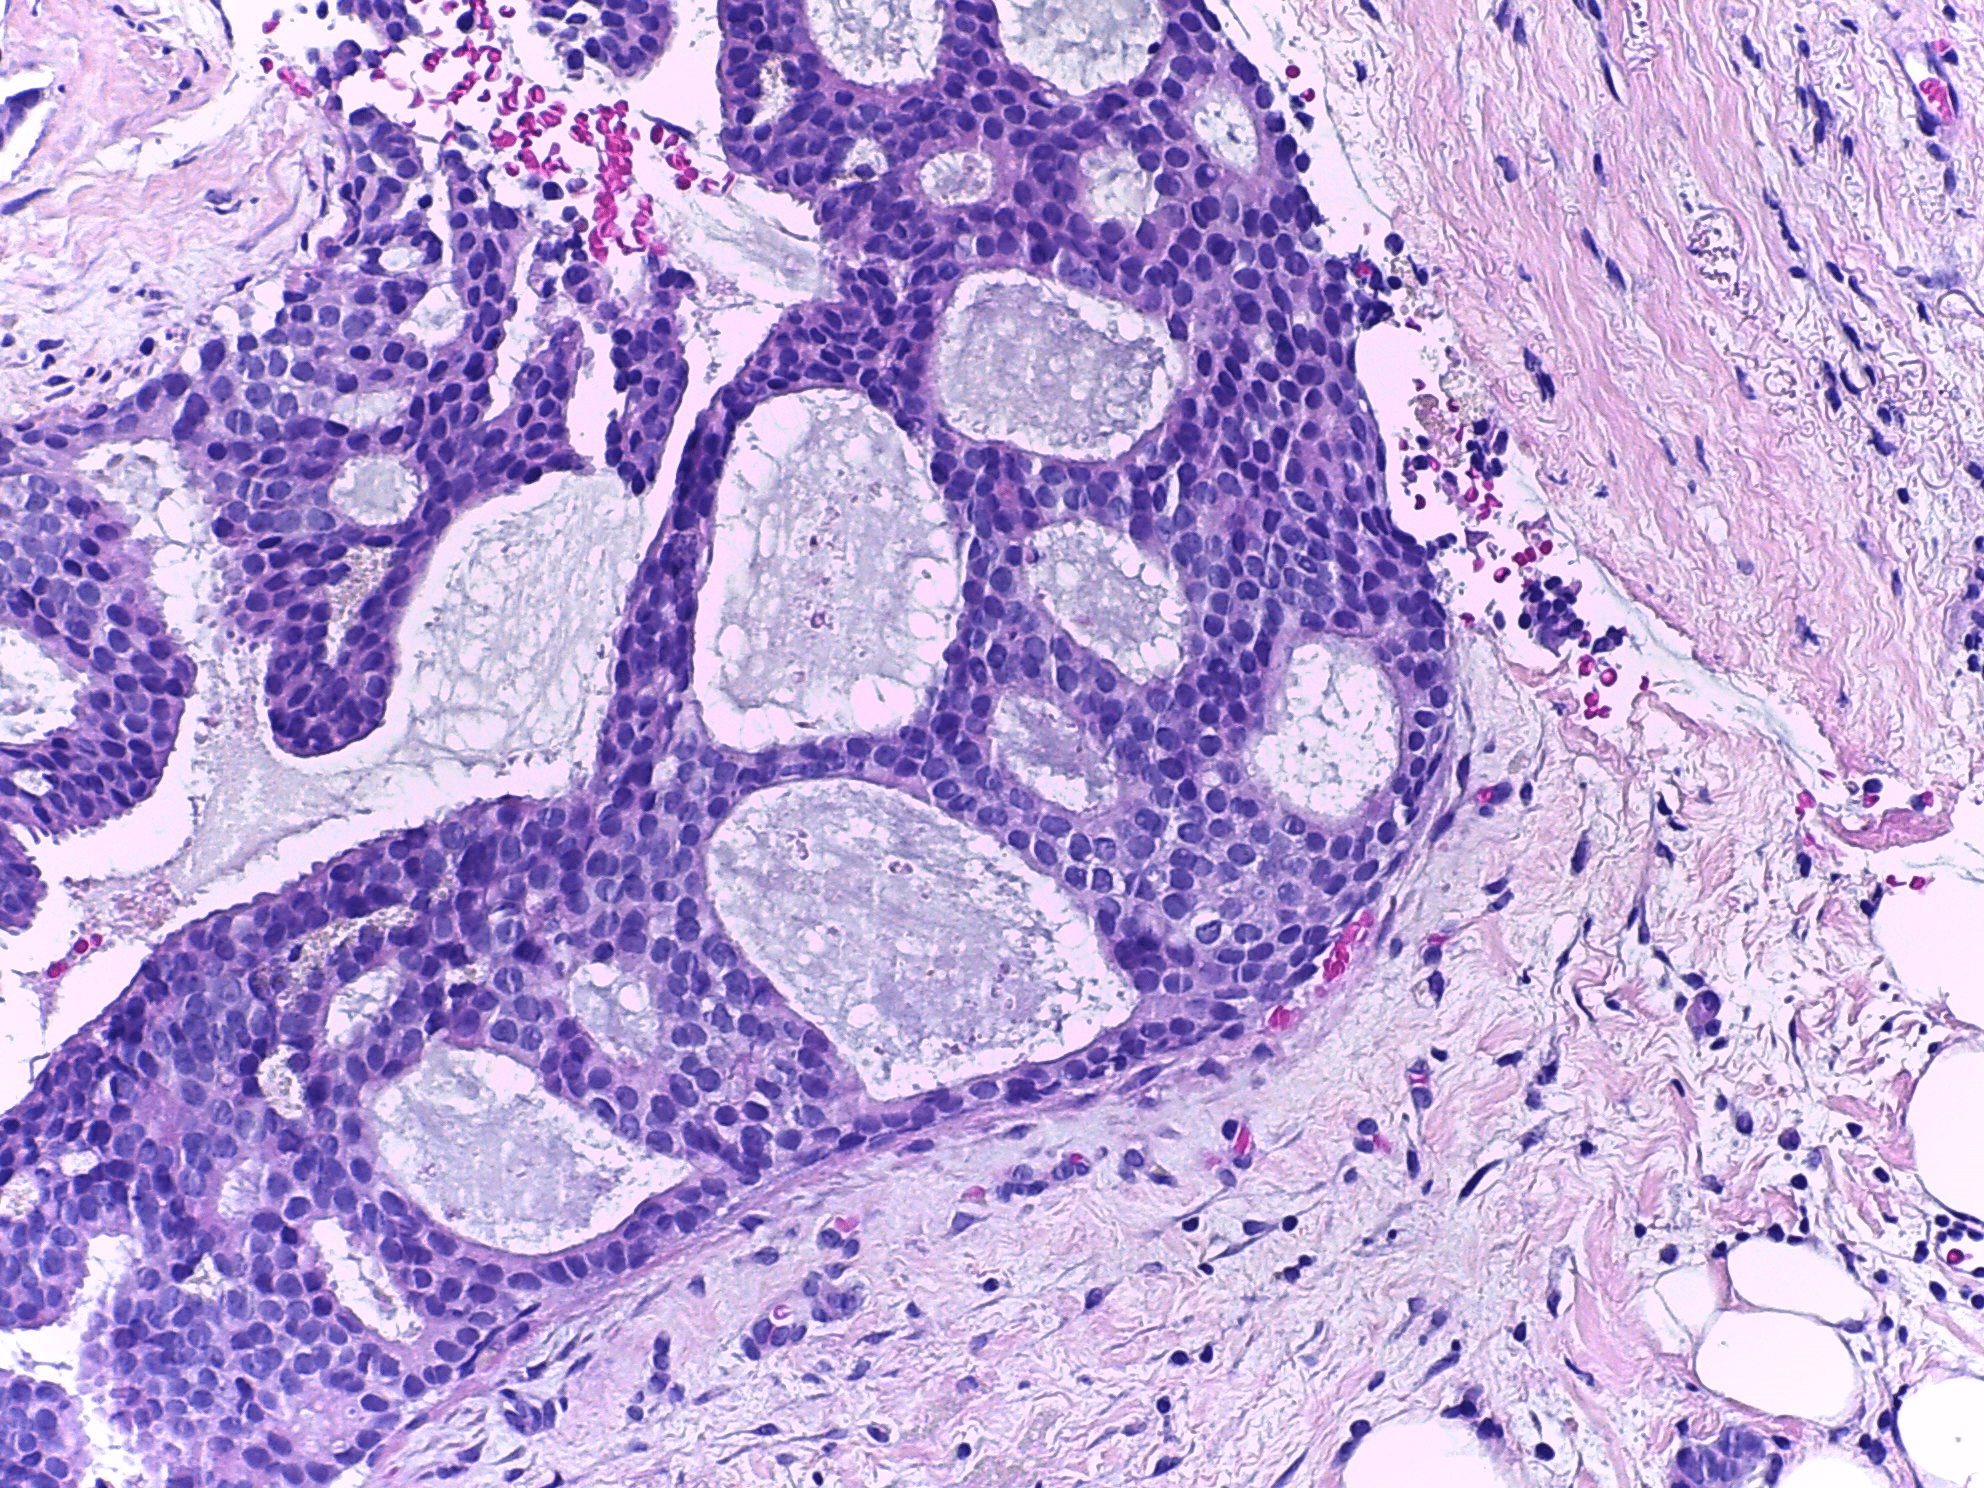

Refer to caption

(a) Benign

(b) Malignant

(c) Benign

(d) Invasive

Figure 1: Representative images from BreakHis and BACH datasets.

The second dataset was ICIAR2018 Grand Challenge on Breast Cancer Histology images (BACH). The BACH dataset comprises of 400 histopathology images of breast cancer. Each image of this dataset is of three channels and the size of 2048 ×\times 1536 pixels. The original BACH dataset contains four classes viz.𝑣𝑖𝑧viz. normal, benign, in situ and invasive. We clubbed normal and benign classes to form one class for our binary classification problem, whereas the other class is formed by clubbing in situ and invasive classes together. Figure 1 shows representative images from BreakHis and BACH dataset.